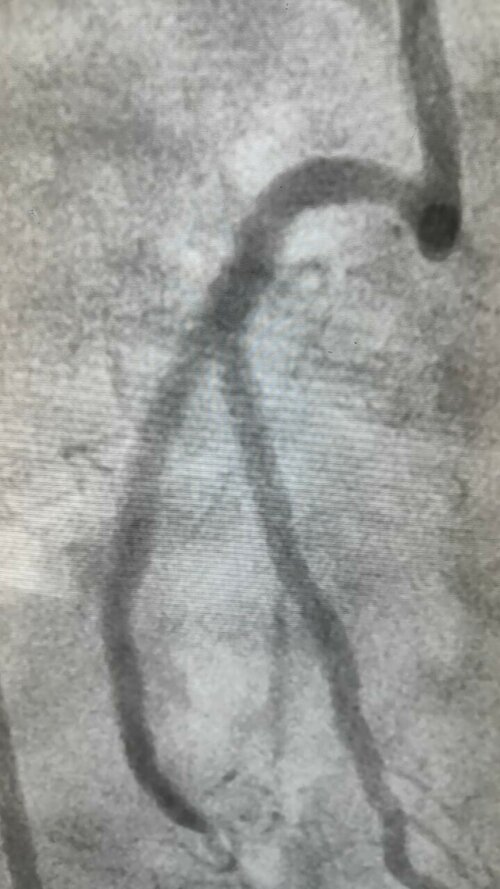

Success in Complex Left Main Bifurcation Angioplasty by Dr. Hasmukh Gujar, Cardiologist

Dr. Hasmukh Gujar, a skilled Cardiologist near Swargate on Satara Road, has achieved remarkable success with a complex left main bifurcation angioplas...